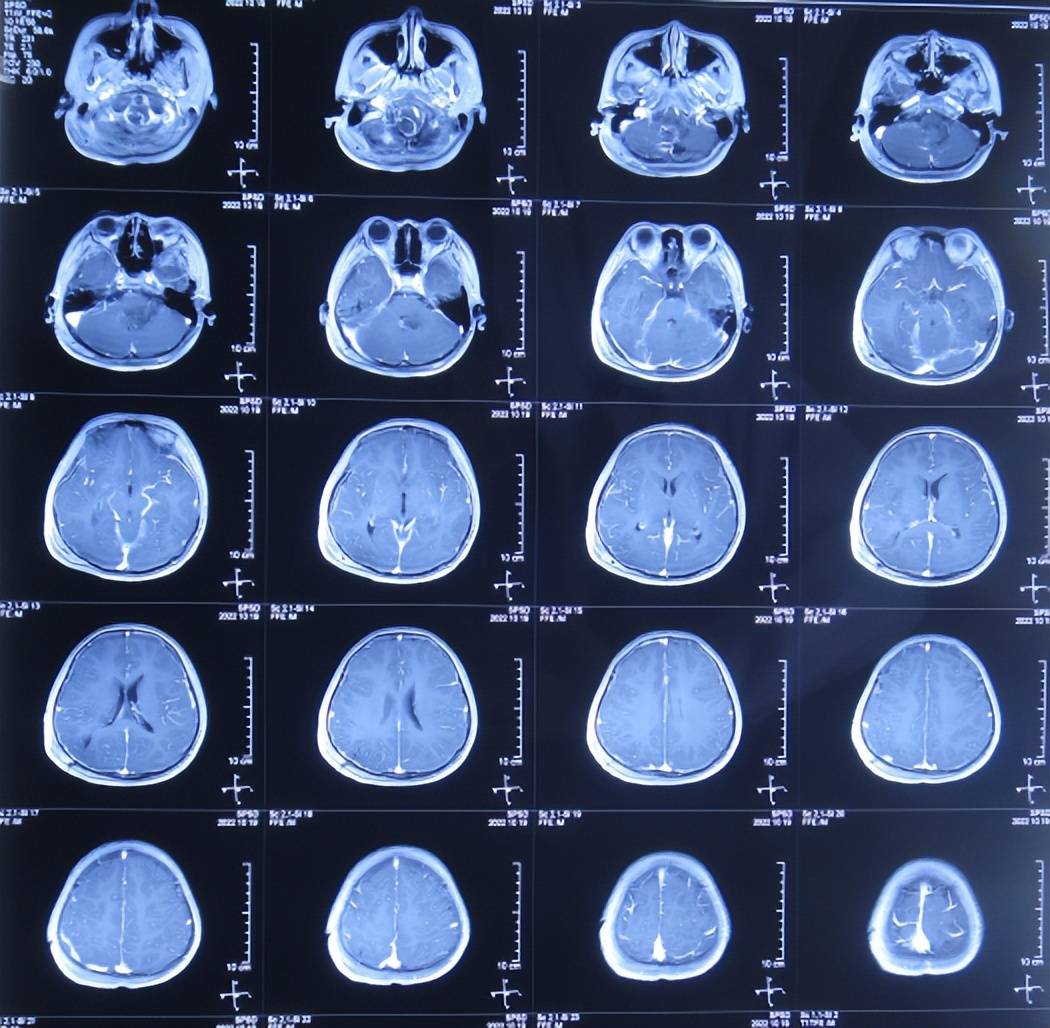

图-5: 2022年10月17日术后颅脑CT

进一步检查颅脑血管造影( 图-6 )和颅脑核磁增强( 图-7 )示延髓偏后方占位伴延髓损伤,考虑中线胶质瘤伴出血可能性大。

图-7: 2022年10月17日颅脑核磁增强

但脑室腹壁外引流术后2天即2022年10月19日,患儿症状并未明显减轻,查颅脑核磁示脑室有缩小( 图-8 ),计划明日进行脑瘤切除术。

图-8: 2022年10月19日颅脑核磁增强